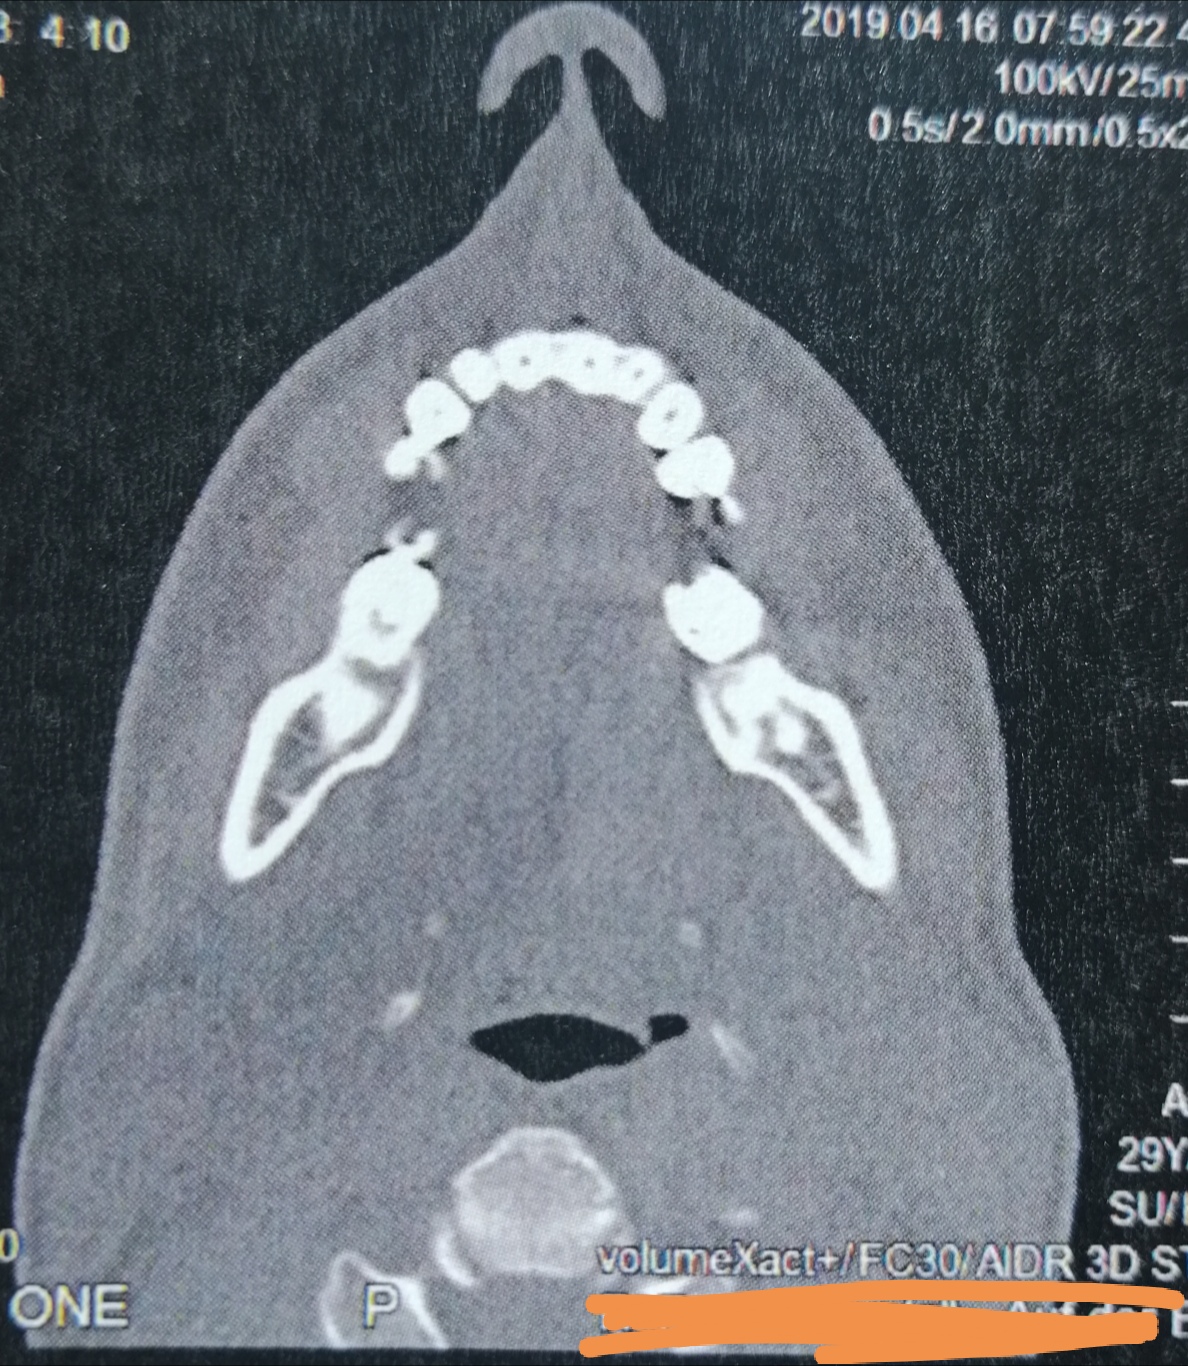

CT der Nasennebenhöhlen /Nase, alles ok? (kernspintomographie)